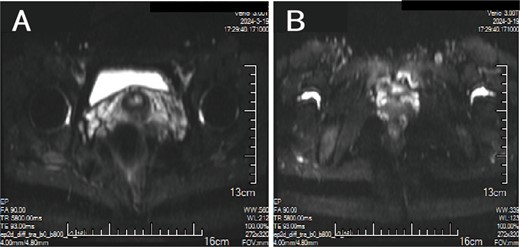

A 38-year-old married female patient presented with a lump near her anus 10 years ago, without apparent cause or symptoms such as redness, swelling, heat, or pain, nor cough, abdominal pain, or diarrhea. No specific treatment was administered. The patient now reports that the lump has grown larger and is accompanied by increasing swelling and discomfort. Seeking further diagnosis and treatment, she visited our outpatient department, where she was admitted with the condition “perianal lump.” Physical examination revealed a body temperature of 36.5°C, pulse rate of 86 beats/min, respiratory rate of 19 beats/min, and a blood pressure of 134/85 mmHg. Admission symptoms include perianal swelling and pain, with itching; no signs of fever, chills, rupture, or pus discharge; bowel movements once or twice daily, and normal urination. The patient has one child and underwent a lateral epidural resection 12 years ago due to natural childbirth. Specialist examination revealed a 4-cm lump with a hard texture at 7–11 o’clock next to the anus, and a radial surgical incision at the 7 o’clock anal margin. Digital rectal examination found no lump, depression, or induration in the anus, and no blood on fingertips. The initial diagnosis was a perianal lump. Auxiliary examinations included ultrasound, which revealed a 4-cm lump in the subcutaneous soft tissue near the anus with minor blood flow signals within and around it, suggestive of an inflammatory lesion (Fig. 1A and B); and pelvic MRI, which suggested a left perianal lump consistent with a perianal abscess (Fig. 2A and B). Under spinal anesthesia, the perianal lump was removed, and postoperative pathology confirmed the presence of endometriosis (Fig. 3).

MRI: (A, B) A cluster of low/high mixed signals such as T1 and T2 can be seen on the left side of the anus, and the DWI signal is partially increased.